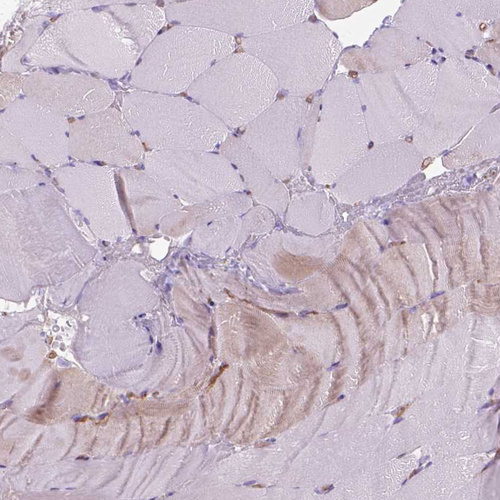

Immunohistochemical staining of human colon shows strong membranous positivity in glandular cells.